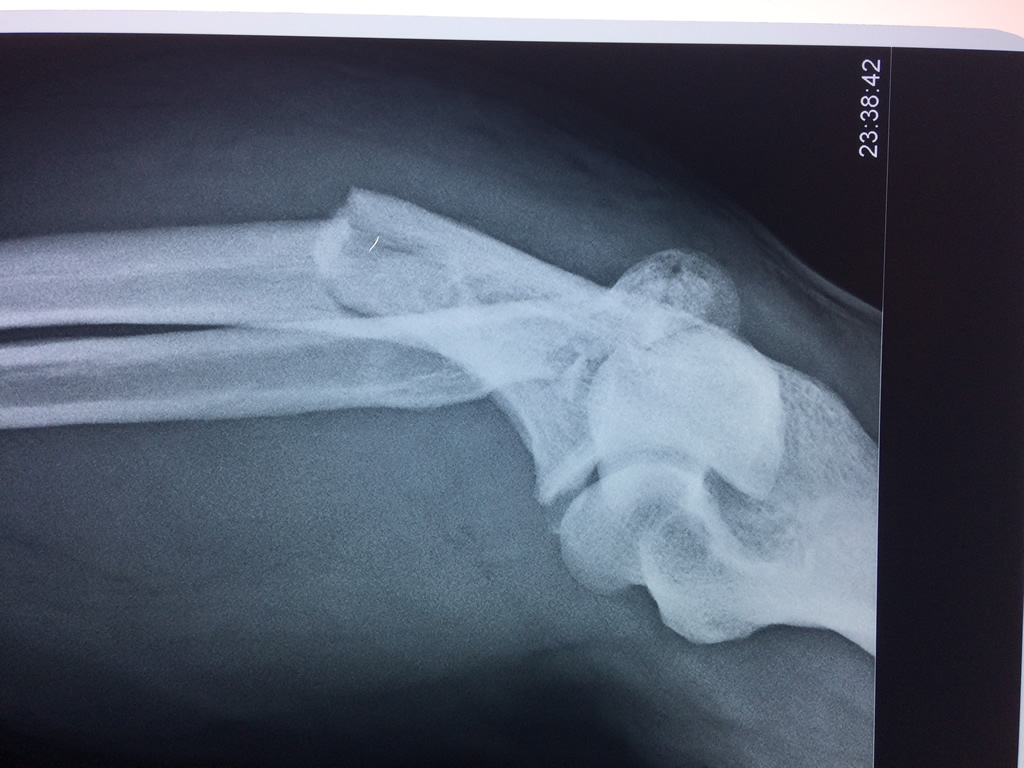

Cirugías de Húmero - Codo

En anatomía humana, la articulación del codo es la que une el brazo con el antebrazo, conectando la parte distal del hueso húmero con los extremos proximales de los huesos cúbito y radio.

La articulación principal que constituye el codo se denomina humero radio-cubital y puede dividirse en dos partes bien diferenciadas, la articulación humero-radial y la humero-cubital.